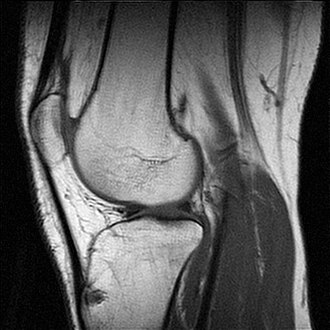

MR-snimka ljudskog koljena